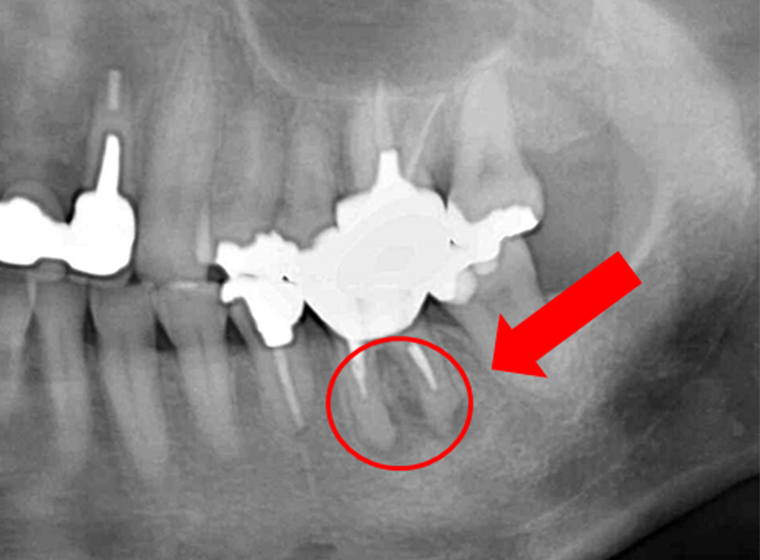

奥歯の症例

それぞれ、左が術前で右歯術後の写真です。根の先に大きな膿のかたまり「根尖病巣」ができており、噛めないくらいの強い痛みと腫れがありました。術後は根尖上病巣が消失し、不快症状もありません。根管治療後に歯根の先端まで白く写っていて、充填材が届いていることが確認できます。抜歯が検討されるくらいの難症例でしたが、「できるだけ歯を抜かない」ことを心がけている当院だからこそできた治療です。